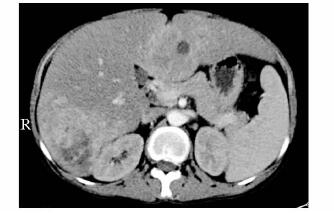

结果  患者为27岁男性, 有低血糖、高乳酸血症、高尿酸血症和高脂血症的典型临床表现, 肝穿刺活检支持GSD Ia。患者G6PC基因第2个外显子检测到c.248G > A(p.R83H)错义突变, 第5个外显子检测到c.674T > C(p.L225P)错义突变, 患者父亲和母亲分别是携带c.674T > C(p.L225P)及c.248G > A(p.R83H)突变的杂合子。采用Polyphen 2和SIFT软件对新发现的c.674T > C(p.L225P)突变蛋白功能进行预测, 提示为致病突变, 可能损害葡萄糖-6-磷酸酶蛋白功能。

Results  The patient was a 27-year-old male Chinese GSD with typical symptoms of hypoglycemia, hyperlactaci-demia, hyperuricemia and hyperlipidemia, and the diagnosis of GSD Ia was confirmed by liver biopsy. Missense mutations of c.248G > A (p.R83H) in the second exon and c.674T > C (p.L225P) in the fifth exon were detected in G6PC gene in this patient, which were separately carried in his mother and father, respectively. The pathogenicity of novel mutation c.674T > C(p.L225P) was supported by Polyphen2 and SIFT software analysis, which showed that the mutation might damage the function of glucose-6-phosphatase protein.